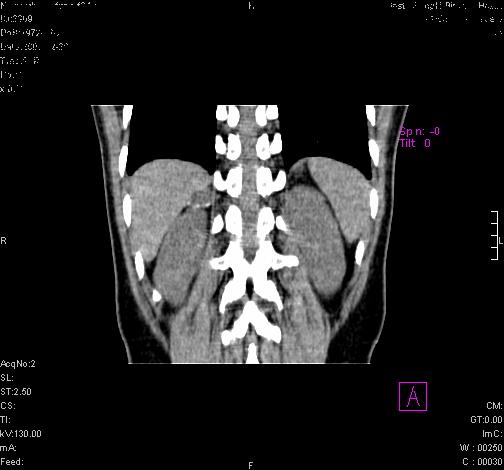

标题: CL0340:【】肾上腺囊肿,比较典型。

患者为年轻女性,查体发现右侧肾上腺囊性占位。无临床体征。

这么漂亮的图像,一看一目了然。典型的右侧肾上腺囊肿,周围有钙化。感谢搂主!

“肾上腺囊肿组织学分为4类:1)内皮细胞性,2)假性囊肿,3)寄生虫性,4)上皮细胞性。其中内皮细胞性最为常见。假性囊肿多为肾上腺内出血后遗留囊腔,囊壁无上皮细胞。寄生虫性多为包虫病引起。上皮性则很少见。”

这么明显的弧形钙化,多考虑包虫病所致的寄生虫性囊肿。

这么漂亮的图像,一看一目了然。典型的右侧肾上腺囊肿,周围有钙化。感谢搂主

右侧肾上腺囊性密度灶囊壁有钙化。考虑肾上腺囊肿,结核?